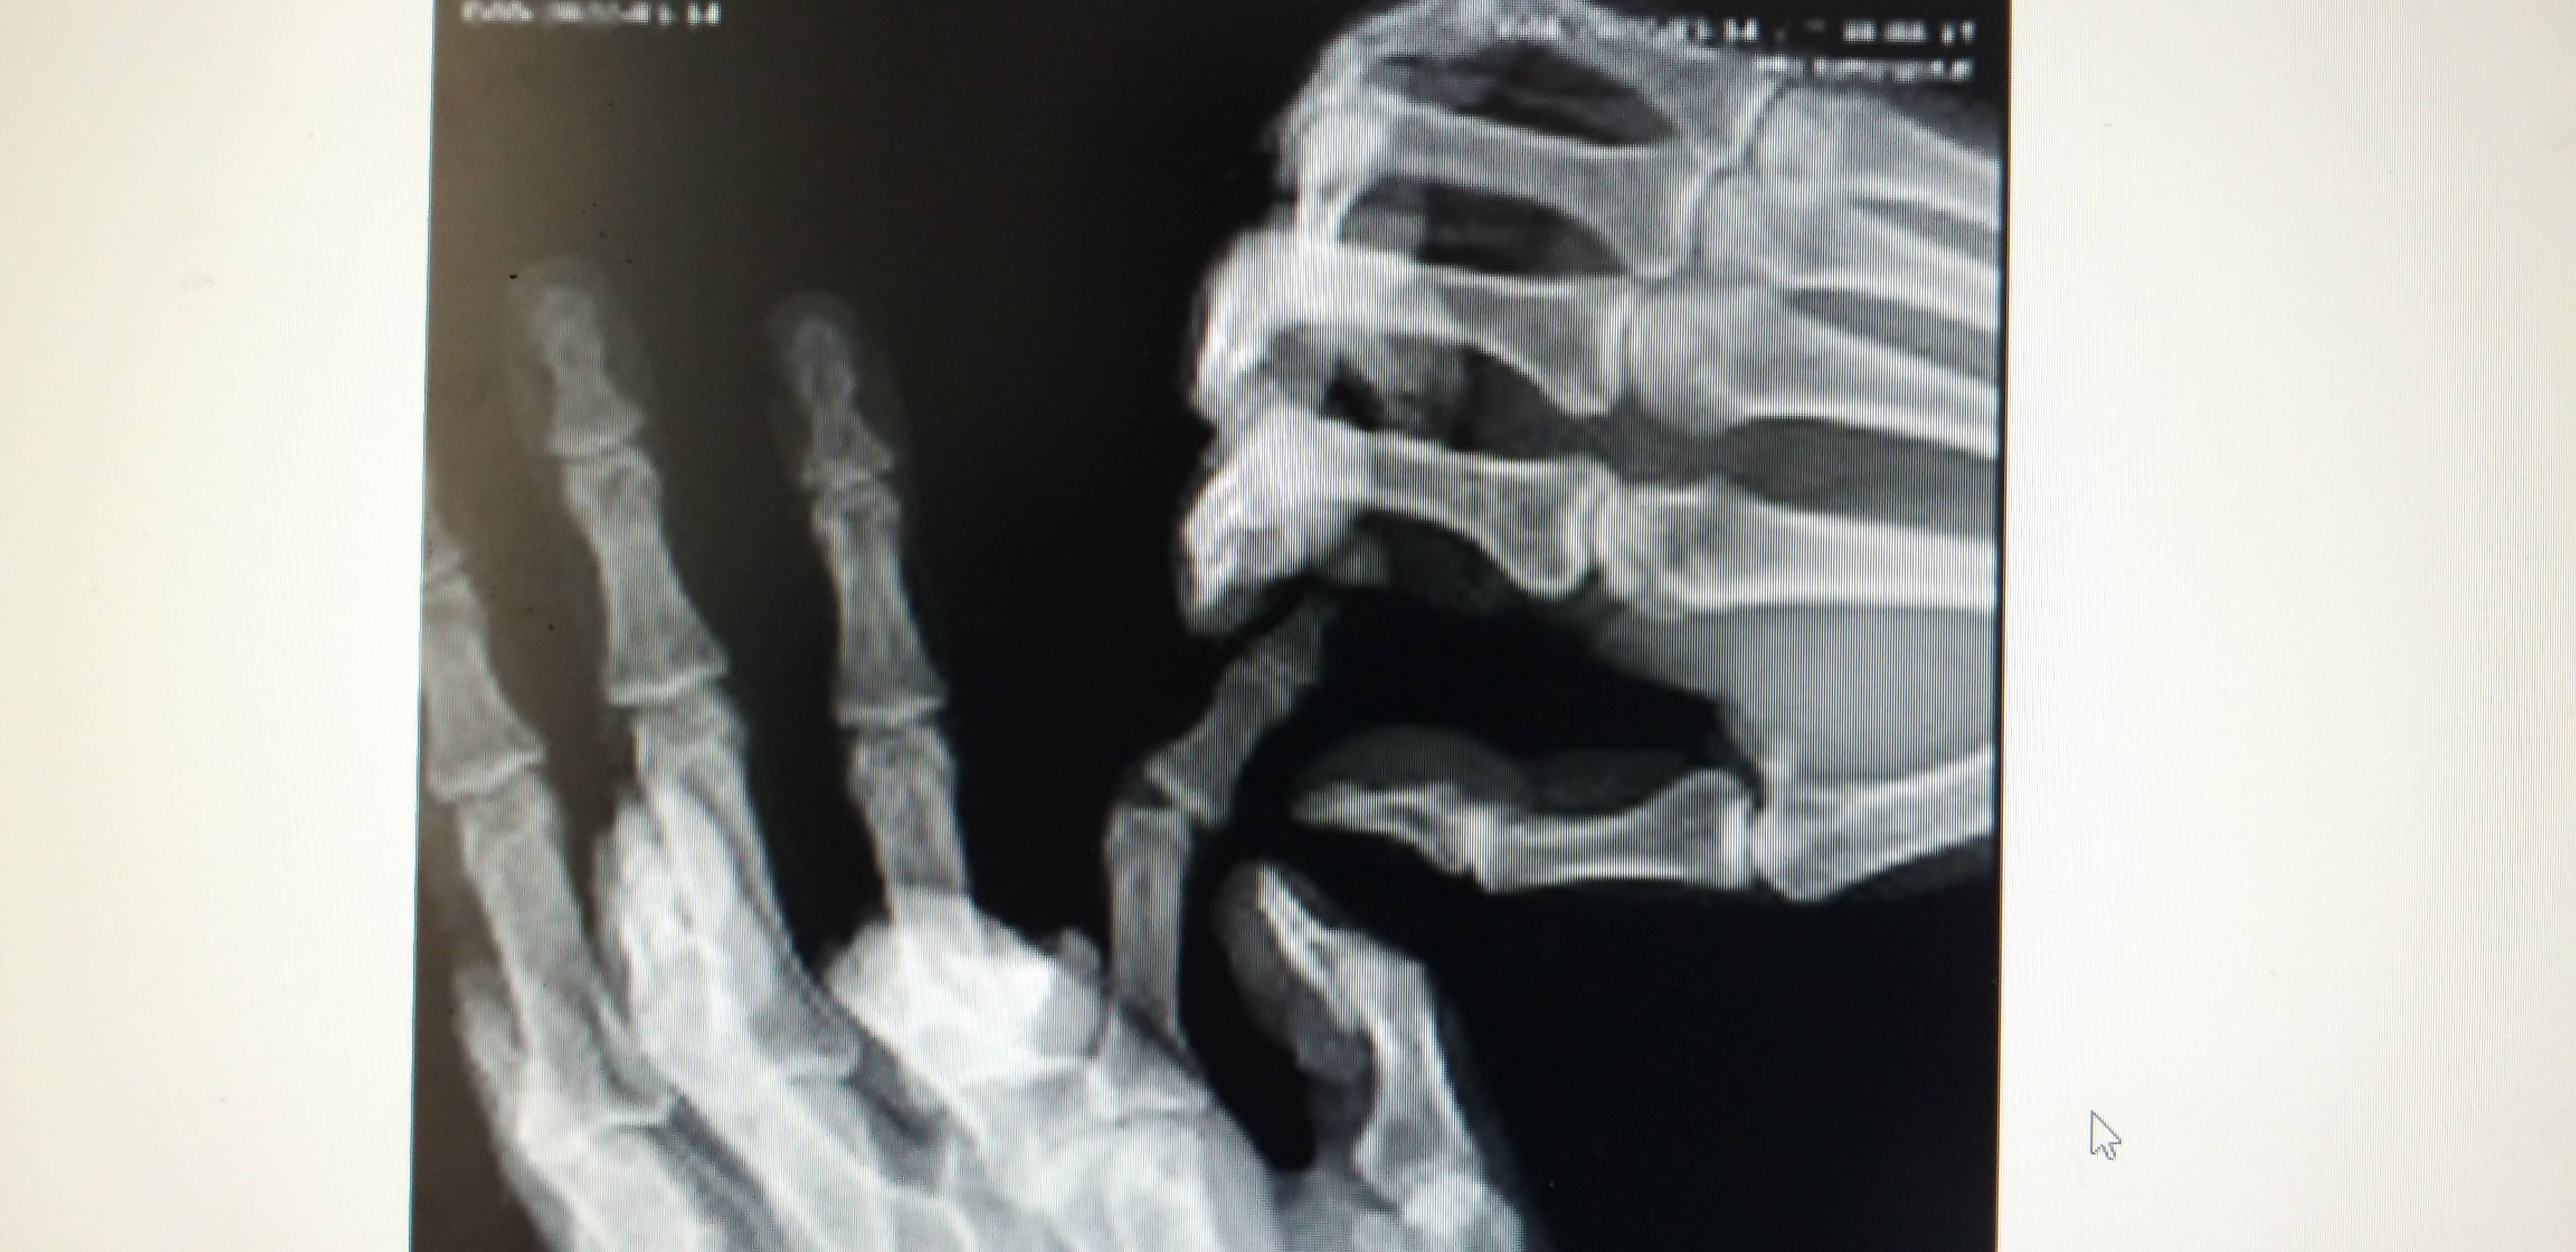

수지전문 병원이 집근처에 있어 바로 검사를 시행하였습니다. 아래사진에서 보듯이 X-RAY 상에서 손가락이 옆으로 휘어져 있습니다.

의사선생님 말씀으로는 인대가 완전 파열된 상태이며 인대가 원래 뼈에 붙어있는 상태에서 충격이나 골절로 파열될때 뼈조각이 같이 떨어지는 경우가있다고 하셨고 나의 상태도 손가락 인대 완전 파열과 뼈조각 제거 수술을 바로 진행해야 된다는 진단을 받았습니다.

참고로 수지전문 병원마다 의사의 소견이 틀리며 처음으로 간 병원은 X-ARY 초음파 검사만 하고 바로 수술결정을 내렸습니다.